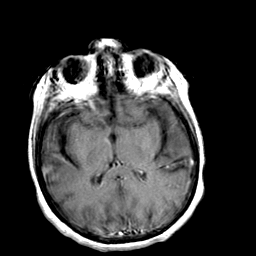

Creutzfeld-Jakob disease: gadolinium enchanced T1-Weighted MR -- Slice #12

[Home][Help][Clinical] Slice 12